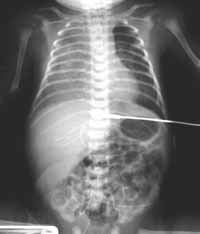

His initial chest x-ray (below) was markedly abnormal:

WHAT IS YOUR INTERPRETATION OF THIS FILM?